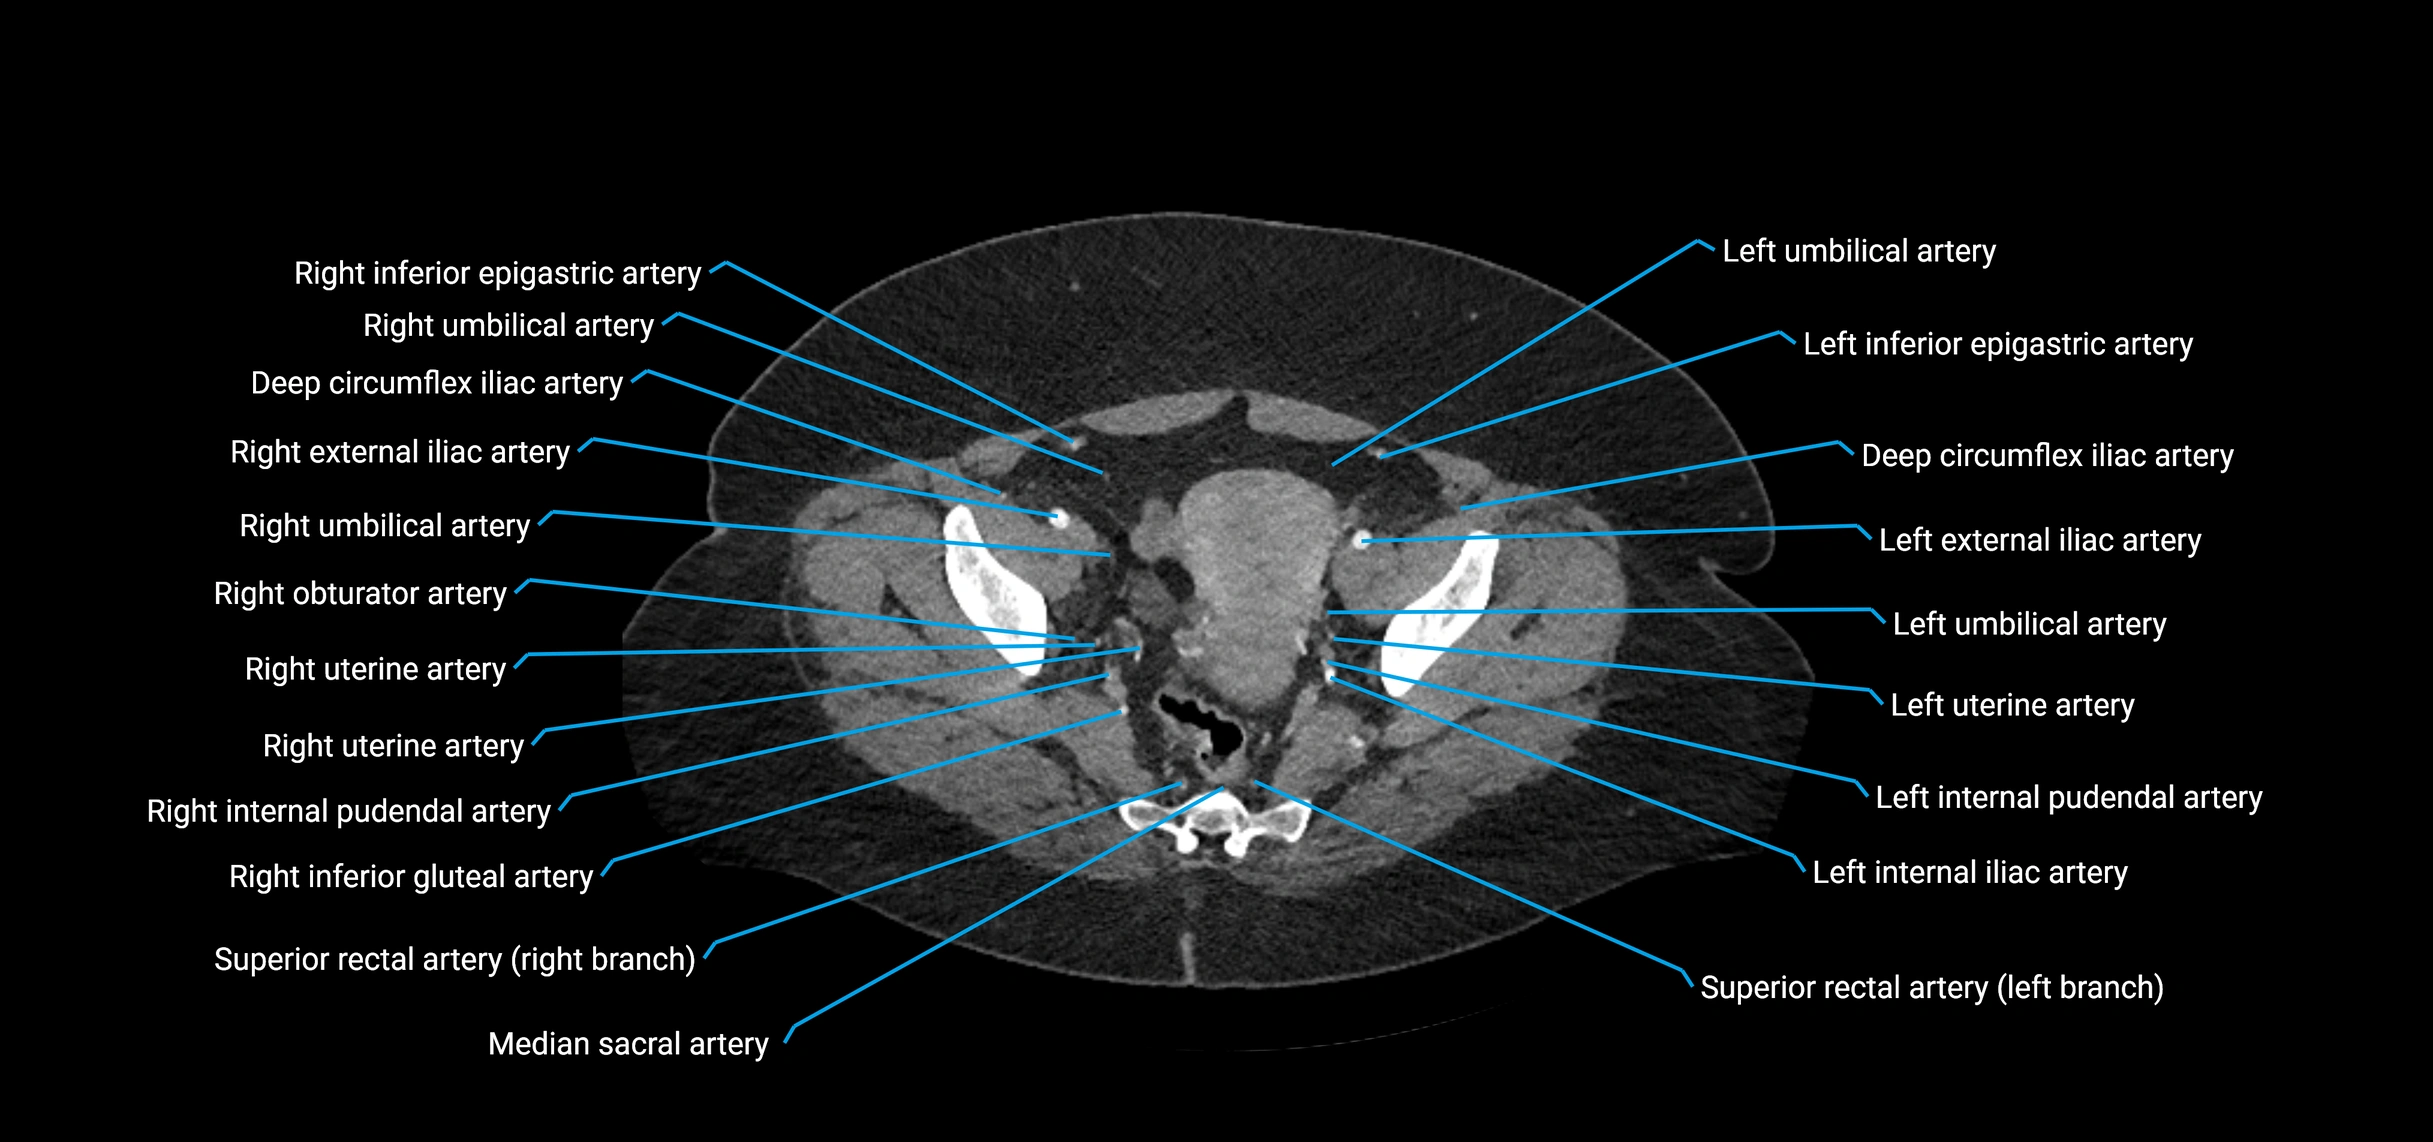

CT images

image

Contrast-enhanced CT (CTA):

• Gold standard for abdominal aortic imaging

• Provides excellent detail of lumen, wall, aneurysm, thrombus, and branch vessels

• Multiplanar and 3D reconstructions help in aneurysm measurement, stent graft planning, and dissection evaluation